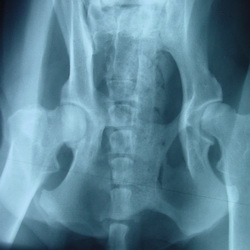

HD-Untersuchungsstelle (Zuchtuntersuchungen, ED,…)

Hüftgelenkoperationen